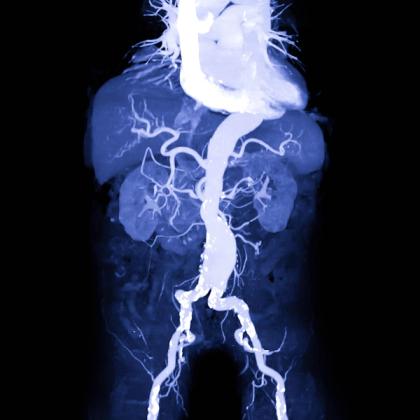

Abdominal aortic aneurysms (AAAs) are potentially life-threatening and have a poor prognosis if ruptured. Arterial aneurysms are defined as a permanent localised dilatation of the vessel, enlarging significantly compared to a relatively normal diameter of the adjacent artery. An AAA is characterised by abnormal focal dilation of the abdominal aorta that is often detected incidentally or only at the time of rupture. In this episode, Dr Roger Henderson looks at AAA risk factors, clinical presentations, diagnostic investigations, screening, treatments and prognosis.

- Abdominal aortic aneurysms (AAAs) represent a critical and potentially life-threatening vascular condition, characterised by abnormal dilation of the abdominal segment of the aorta.

- AAA is usually defined as having an aortic diameter of 3 cm or greater, with most AAAs arising from below the level of the renal arteries.

- Computer tomography angiography is the recommended definitive imaging modality for AAA rupture, as it provides detailed anatomical information and is helpful with preoperative planning.